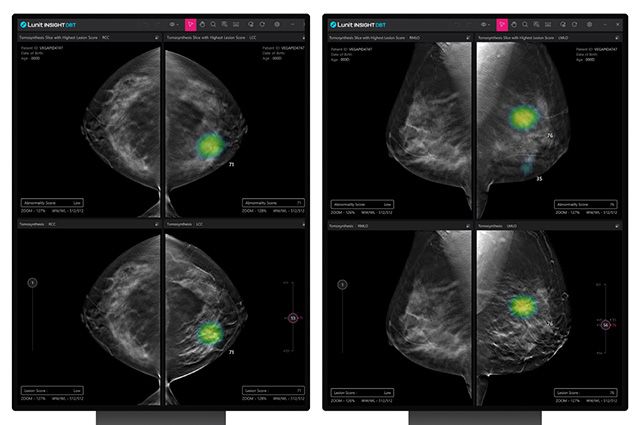

‘루닛 인사이트 DBT’는 디지털 유방단층촬영술(DBT)로 얻은 3차원 유방 영상을 AI로 분석해 의료진의 판독을 보조하는 솔루션이다. 해당 솔루션은 기존 2차원 유방촬영술보다 병변을 입체적으로 파악할 수 있어, 치밀 유방을 가진 환자에 대한 진단 정확도를 높일 수 있는 것이 특징이다.

회사에 따르면, 루닛 인사이트 DBT는 지난해 북미영상의학회(RSNA)에서 발표된 미국 에모리대학교병원 연구 결과에서 AI 모델의 진단 정확도를 수치로 나타내는 지표인 AUC(곡선하면적) 0.92를 기록했다. 해당 연구는 인종, 연령, 유방 밀도 등 다양한 조건에서도 높은 진단 성능을 유지한 결과를 보고했으며, 석회화 병변처럼 판독이 까다로운 유형에서도 안정적인 결과를 보였다고 설명했다.